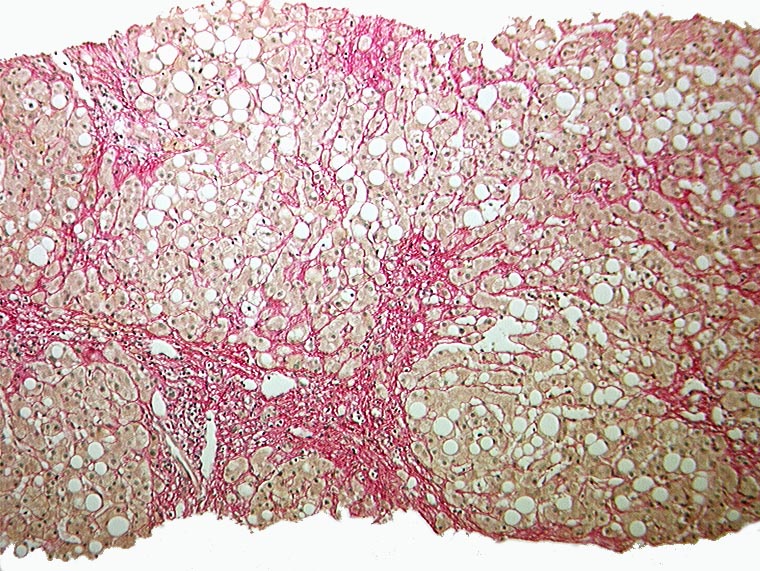

Floride alkoholische Steatohepatitis

Makroskopie

Pathologischer Befund